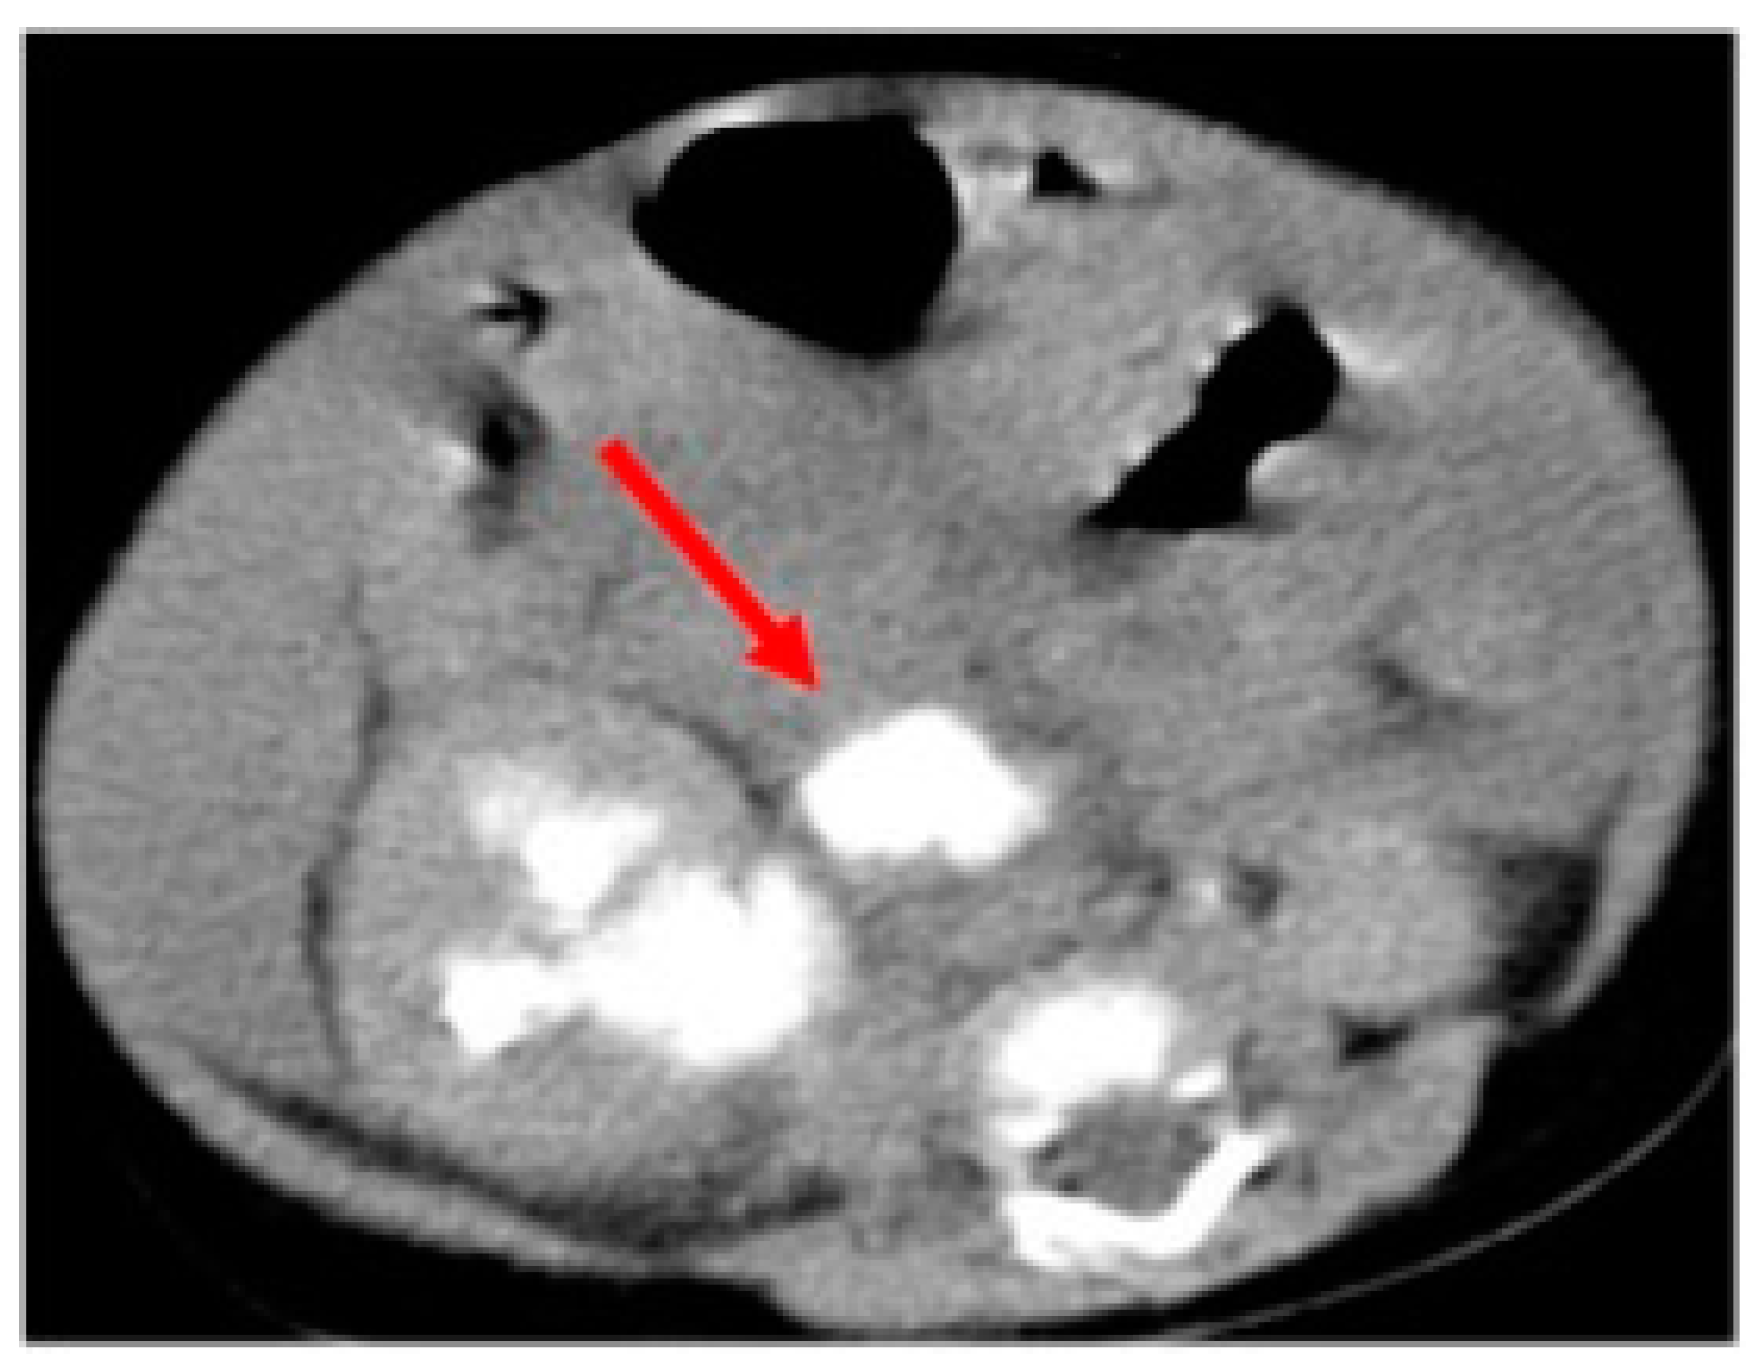

Voiding cystourethrography (VCUG) showed neither a vesicoureteral reflux (VUR) nor anomalies on the lower urinary tract. In the case of suspicion of urinary tract rupture, we decided to perform a computed tomography (CT) scan that highlighted an abundant and diffuse ascitic effusion, a right pararenal fluid collection opacified on late urographic scans (Figure 1), a compressed and thread-like renal pelvis, and no ureteric opacification.

Figure 1.

Computed tomography scan underlining the spontaneous pelvic rupture with the pararenal fluid collection opacified on late urographic scans (arrow).